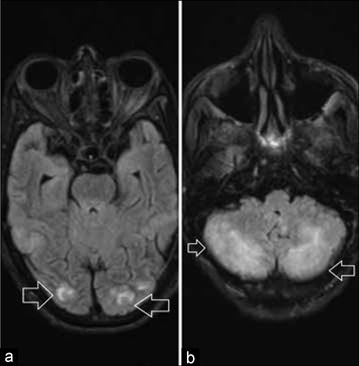

后可逆性脑病综合征(PRES)是一种可逆性临床综合征,通常以一系列神经系统表现和反映血管源性水肿的独特神经影像学发现为特征。PRES 的临床表现多种多样,包括肾功能衰竭、血压波动、使用细胞毒性药物、自身免疫性疾病和子痫。高钙血症很少与 PRES 有关。我们报告了一名因高钙血症继发 PRES 的肺癌患者。

Posterior reversible encephalopathy syndrome (PRES) is a reversible clinical syndrome usually characterized by a range of neurological manifestations and distinctive neuroimaging findings reflecting vasogenic edema. PRES has been described in the context of various clinical settings including: renal failure, blood pressure fluctuations, use of cytotoxic drugs, autoimmune disorders and eclampsia. Hypercalcemia is rarely associated with PRES. We report a patient with lung cancer presenting as PRES secondary to hypercalcemia.